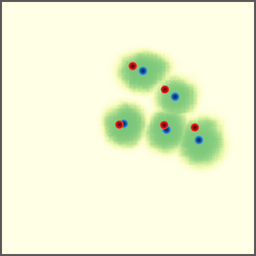

Shift-Invariant Tracking. The POINT network benefits from the shift invariant property of the convolution operation, which makes it less sensitive to the in-plane offset of the DRRs. Figure 8 shows some tracking results from the POINT network. Here the odd rows show the (a) X-ray and (b-d) DRR images. The heatmap below each DRR shows the tracking result between this DRR and the leftmost X-ray image. The red and the blue marks on the X-ray and DRR images denote the POIs. The red and the blue marks on the heatmaps are the ground truth POIs and the tracked POIs, respectively. The green blobs are the heatmap responses and they are used to generate the tracked POIs (blue) according to Equation (7). The numbers under each DRR denote the mPD scores before and after the tracking. As we can observe that the tracking results are consistently good, no matter how much initial offset there is between the DRR and the X-ray image. This shows that our POINT network indeed benefits from the POI convolution layer and provide more consistent outputs regardless of the in-plane offsets.

Refer to caption

(a)

(b) 13.6 \rightarrow 7.3

(c) 22.9 \rightarrow 9.0

(d) 37.1 \rightarrow 7.8

(e)

(f) 19.5 \rightarrow 8.7

(g) 26.0 \rightarrow 9.5

(h) 41.1 \rightarrow 11.4

(b)

(c)

(d)

Figure 8: POI tracking results. (a) X-ray image. (b-d) DRR images with different in-plane offsets. The heatmaps of the tracking results are all aligned with the X-ray images and appear similar, showing the shift-invariant property.